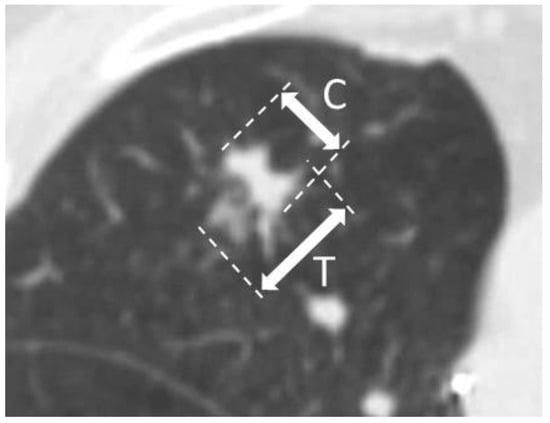

2.5. Prediction of CTR